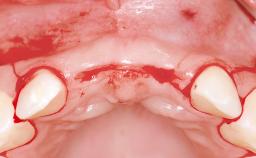

Replacement of Four Incisors with a Fixed Partial Denture on Two Narrow-Neck Implants after Implant Failure

| Soft Tissue Anatomy | Intact | Defective | |

| Bone Volume | Horizontally and vertically sufficient | Horizontally deficient | Deficient vertically or deficient vertically AND horizontally |

| Bone Volume | Deficient vertically or deficient vertically AND horizontally |